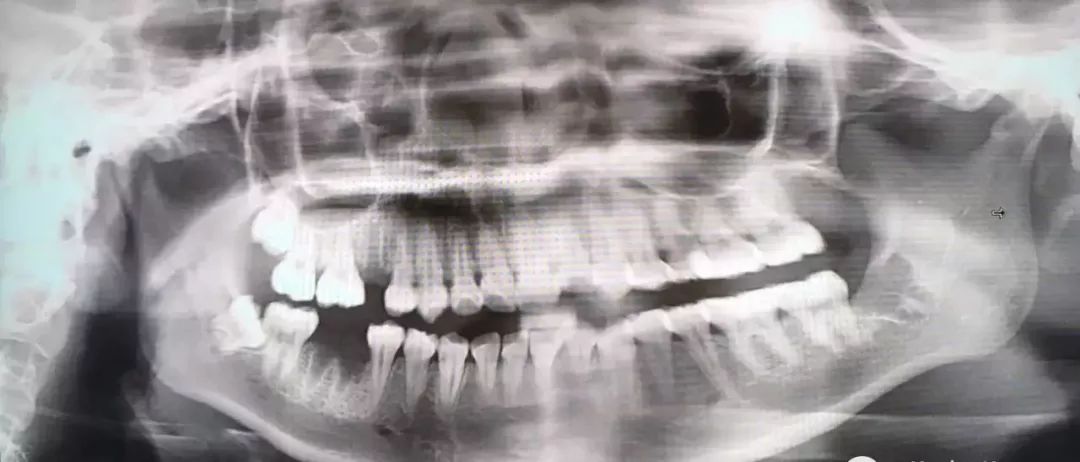

最后介绍一下,牙根弯曲,骑在下颌管上的智齿...由于下颌管内神经丰富,拔除的时候需要极度小心,而且看长相也知道这种模式的拔牙,非常难也非常贵!

也是先切开牙肉,翻开并露出骨头,切下牙冠后取出,再处理下面的牙根。

把牙根分成两半,根据牙根的走向,分别小心地撬出来,这个过程十分考验技术,要谨慎避免损伤到下颌神经...

1.2 恰当检查 包括高质量的X线片,它不仅能提供牙齿的清晰图像,牙根的轮廓和解剖以及牙周骨质情况,还能提供牙齿与邻牙和其他结构之间的关系,其中尤其是下颌骨下缘、下颌骨升支以及下牙槽神经束之间的关系。